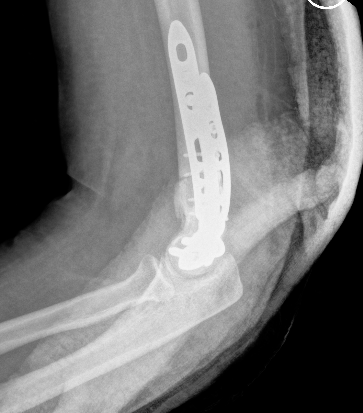

Arthroplasty

Indications

Elderly

Comminuted, osteoporotic distal humerus fracture

Total Elbow Arthroplasty versus ORIF

- RCT 42 patients > 65 years of age

- ORIF verus semiconstrained TEA

- 5 ORIF patients converted to TEA intraoperatively

- better elbow score at 2 years

- no difference in DASH score at 2 years

- mean ROM 107 TEA and 95 ORIF